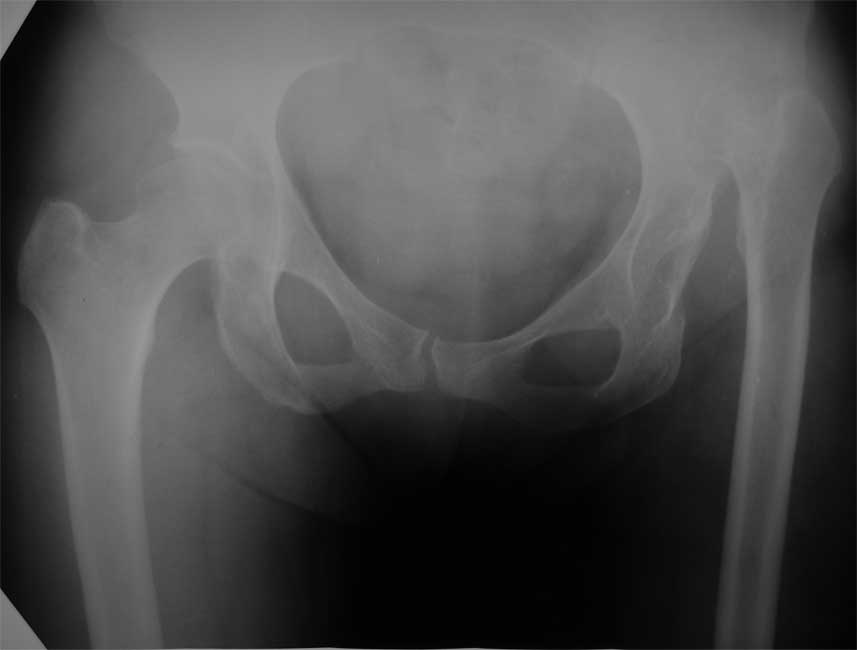

Госпитализирована пациентка 54 лет с высоким врожденным вывихом левого бедра.

Основная жалоба - укорочение левой н/конечности (до 6 см), движения в полном объеме, боли в суставе нет. Вопросы: необходимо ли вообще выполнять THR или попытаться отговорить пациентку? Если делать, то как, дозированно низвести в аппарате, одномоментно с укорачивающей резекцией, потом удлинить бедро? насколько сильно пострадает коленный сустав (сейчас не беспокоит?